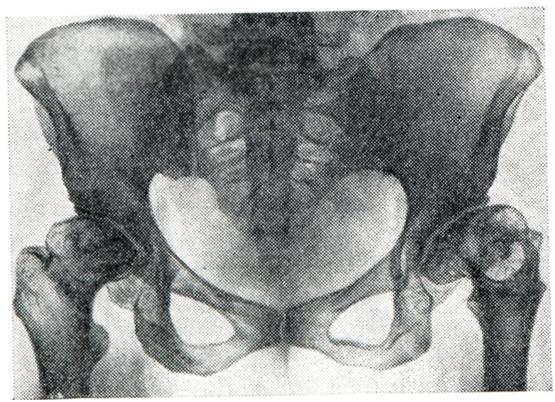

При старении хряща в нем доминирует анаэробный гликолиз, в результате чего увеличивается содержание лактата и уменьшается рН. Это увеличивает активность указанных ферментов, так как оптимальное их действие бывает в кислой среде, и деградация компонентов межклеточного вещества хряща еще больше усугубляется. В ответ на увеличенную деполимеризацию протеино-полисахаридных комплексов и уменьшение компонентов хряща наступает пролиферация хондроцитов и усиление синтеза хондроитинсульфата. Таким образом, дистрофия хряща постепенно про¬грессирует, поверхностный слой его приобретает клочковидную структуру. Кроме того, при А. изменяются свойства синовиальной жидкости, к-рая является хорошим смазочным средством, особенно за счет гиалуроновой кислоты. Это тоже способствует развитию артроза. Синовиальная оболочка, богатая соединительнотканными элементами, кровеносными и лимфатическими, сосудами, нервами, тоже принимает участие в развитии артрозов, особенно при появлении реактивных воспалительных реакций. При электронномикроскопическом изучении синовиальной оболочки выделены два типа клеток: тип А и тип В. Клетки типа А являются преимущественно абсорбтивными и имеют способность фагоцитировать, а клетки типа В в основном вырабатывают комплексы гиалуроновой кислоты и протеинов. При артрозах активность этих клеток вначале усиливается, а по мере прогрессирования процесса ослабевает. Причины, вызывающие пуск этого механизма, неизвестны. Полагают, что может иметь значение генетическая предрасположенность, обусловленная дефектом в синтезе полисахаридов и ферментов хряща. В этиологии и патогенезе вторичных артрозов главную роль играют травмы, нарушающие целость или конгруэнтность (соответствие) суставных поверхностей. Другими причинами вторичных артрозов являются врожденные дисплазии и приобретенные нарушения статики, перенесенные артриты, заболевания эпифизов костей, заболевания обмена веществ (например, подагра, охроноз, болезнь Кашина — Бека), эндокринные заболевания (гипотиреоз, сахарный диабет и другое). Врожденные и приобретенные дефекты хряща и других элементов костно-суставного аппарата в сочетании с продолжающейся или даже увеличивающейся нагрузкой на суставы могут через определенный период времени привести к развитию артрозов. Учитывая то обстоятельство, что травмы и микротравматизация, аномалии статики (варусное или вальгусное положение бедер, голеней и стоп, плоскостопие, врожденный вывих или дисплазия бедра, кифоз, лордоз, сколиоз и другое), перенесенные болезни костей (асептические некрозы) и суставов (артриты) и некоторые другие состояния весьма часто являются причиной развития артроза, Хаккенброх (М. Hackenbroch, 1968) предложил называть их преартрозами и принимать профилактические меры для предупреждения артроза. В основе патологоанатомических изменений при артрозе лежат прогрессирующие дистрофические и некробиотические процессы в суставном хряще, сопровождающиеся деформацией сочленовных поверхностей костей (рис. 1). Отсюда наиболее распространенный термин — деформирующий артроз. Как правило, в процесс вовлекаются эпифизы костей, что дает основание называть заболевание также остеоартрозом. Деформирующий артроз чаще всего развивается в суставах конечностей. Однако могут поражаться и межпозвонковые диски (смотри Дискартроз). Макроскопическая картина деформирующего артроза зависит от стадии заболевания. В ранней стадии отмечается разволокнение, шероховатость, прежде всего по краям суставного хряща. В дальнейшем наблюдается его истончение, узурирование и образование бугров различных размеров. В далеко зашедших случаях по краям хрящевого покрытия образуются костные разрастания — остеофиты. В участках, воспринимающих давление, поверхность, лишенная хряща, под влиянием постоянного трения как бы отшлифовывается. Костные «шлифы» имеют вид желобообразных вмятин. Все эти изменения обусловливают деформацию сустава. Головка бедра, например, может приобрести грибовидную, цилиндрическую форму или сплющиться. Деформируется также и суставная впадина (рис. 2). Значительные изменения претерпевают связки, синовиальная оболочка, капсула. Внутрисуставные связки становятся утолщенными, разрыхленными. При резком обезображивании сустава они могут подвергнуться некрозу, атрофии или срастись с суставной сумкой. Сосочки синовиальной оболочки увеличиваются в размерах, иногда приобретают древовидный характер. В строме их наблюдается развитие жировой ткани, хряща и кости. Такие сосочки могут отшнуроваться и превратиться в свободные внутрисуставные тела (смотри Суставная мышь). Количество синовиальной жидкости, как правило, резко уменьшено, что явилось поводом характеризовать заболевание как «сухое воспаление суставов». Микроскопическая картина деформирующего артроза складывается из дистрофических изменений суставного хряща (рис.3), сопровождающихся его васкуляризацией и оссификацией со стороны субхондральных отде лов кости. В краевых отделах может наблюдаться избыточная пролиферация хондробластов, которая не столько компенсирует убыль хрящевой ткани, сколько способствует обезображиванию сустава вследствие образования экхондрозов. Экхондрозы со временем подвергаются обызвествлению и замещению костной тканью с формированием столь типичных для артрозов остеофитов. В хряще определяется разволокнение, а также слизистая и жировая дистрофия основной субстанции, снижение содержания кислых мукополисахаридов. Эти изменения сопровождаются образованием многочисленных разрывов и щелей. Одновременно на границах с синовиальной оболочкой и костно-мозговыми пространствами отмечаются явления хондролиза и рассасывания хрящевой субстанции, в результате чего демаскируются проходящие здесь коллагеновые волокна. В поздних фазах возможен некроз хондроцитов и исчезновение волокнистых структур. Крупные очаги некроза хряща встречаются лишь в тяжелых случаях заболевания. В базальных отделах хряща появляются костномозговые полости, окруженные тонкими костными балками.

В субхондральных отделах отмечаются явления лакунарной резорбции и новообразования кости, а в зонах костных «шлифов» развивается остеосклероз. В более глубоких отделах эпифиза преобладает остеопороз с образованием кист, окруженных поясом склерозированной кости. Здесь же встречаются островки хрящевой ткани, которые, по мнению некоторых авторов, представляют собой разрастания хрящевой мозоли, распространяющейся из глубоких отделов необызвествленной зоны суставного хряща. В редких случаях островки хрящевой ткани в виде своеобразных «грыж» выбухают над поверхностью костных шлифов (рис. 4). Фиброзные и костные анктшозы при деформирующем артрозе, в отличие от артритов, не развиваются. Любой артроз развивается и протекает очень медленно и никогда не приводит к тяжелым нарушениям функции суставов и особенно к фиброзному и костному анкилозу. Исключением является тазо-бедренный сустав, отличающийся своими анатомическими особенностями (глубокая суставная яма, вмещающая около 2/3 головки бедренной кости, и сравнительно узкая суставная щель, быстро уменьшающаяся при любом патологическом процессе). В этом суставе очень рано наблюдается ограничение подвижности и вовлечение в процесс мышечно-связочных элементов, что в далеко зашедших случаях нередко является причиной инвалидизации больных. Однако анкилоз и в данном случае не наступает, если к артрозу не присоединяется воспалительный процесс. Любая форма артроза протекает без общих признаков воспаления (ускорение РОЭ, диспротеинемия, повышение температуры, исхудание и другого). Первичный артроз часто сопровождается нарушением жирового обмена, артериальной гипертензией, атеросклерозом и другими заболеваниями. Очень важной чертой артроза является несоответствие между морфологическими изменениями в суставах, наблюдаемыми на рентгенограммах, и клиническими проявлениями болезни. Иногда при незначительных рентгенологических изменениях отмечаются сильные боли и ограничение подвижности. В других случаях при значительных рентгенологических изменениях клинические симптомы оказываются весьма умеренными. Это зависит от нескольких причин. Во-первых, суставной хрящ полностью лишен сосудов и нервов. Поэтому его поражение не дает симптомов до тех пор, пока патологический процесс не выходит за пределы самого хряща. Во-вторых, синовиальная мембрана, суставная капсула, сухожилия и мышцы, имеющие многочисленные нервные рецепторы, воспринимающие боль, не во всех суставах поражаются в одно и то же время и в той же степени. В-третьих, не у всех больных артрозом развивается одинаково быстро: чем медленнее он начинается и протекает, тем менее выражены клинические симптомы, так как организм успевает использовать все компенсаторные приспособления. Суставные симптомы артроза складываются из болей, чувства скованности, быстрого утомления, тугоподвижности, деформаций, хруста и другого. Боли обычно тупые. Они непостоянны, усиливаются в холодную и сырую погоду, после длительной нагрузки (например, к вечеру) и при начальных движениях после состояния покоя («стартовые боли»). В тазо-бедренных суставах боли иррадиируют в паховую либо седалищную область (при этом отмечается напряжение отводящих мышц и сгибателей бедра). Очень часто, особенно при старческих артрозах, вместо болей отмечается лишь ломота и чувство тяжести в костях и суставах. Это ощущение весьма близко к чувству скованности при ревматоидном артрите, но отличается кратковременностью и малой интенсивностью. Истинное ограничение подвижности при артрозе наблюдается редко, чаще речь идет о тугоподвижности и быстрой утомляемости суставов. Все эти симптомы обусловлены нарушением конгруэнтности суставных поверхностей, изменениями (утолщением, кальцинозом, склерозом) в суставной капсуле, сухожилиях и других мягких тканях и спазмом мышц. Деформации суставов лучше всего заметны в дистальных межфалаиговых суставах рук (геберденовские узелки), в тазо-бедренном суставе (состояние флексии, аддукции и внешней ротации бедра), в коленных суставах (утолщение костной ткани за счет краевых остеофитов) и обусловлены костными разрастаниями, а ие набуханием мягких тканей, как при артритах. Причиной хруста суставов (чаще всего коленного) являются неровности суставных поверхностей, известковые отложения и склероз мягких тканей. В отличие от мелкого, крепитирующего хруста при синовитах, для артрозе характерен грубый хруст. Рентгенологическое исследование позволяет диагностировать артроз, установить стадию процесса, провести дифференциальную диагностику. Основным методом исследования при артрозе является рентгенография (смотри Артрография). Помимо стандартной рентгенографии, при наличии показаний применяют томографию, а также функциональную рентгенографию и рентгенокинематографию, которые позволяют определить амплитуду движений, взаимоотношения между суставными отделами костей при различных положениях сустава и так далее. При рентгенологическом исследовании выявляется, что поражение обычно начинается как моноартикулярный процесс, а при множественном поражении изменения в одном суставе превалируют над изменениями в других. Патологический процесс прогрессирует и постепенно становится полиартикулярным. Клинико-рентгенологически можно выделить три стадии в течении артроза. Первая стадия характеризуется незначительными изменениями. Происходит едва заметное сужение суставной щели, особенно в местах наибольшей функциональной нагрузки (например, в латеральном отделе щели тазо-бедренного сустава и в медиальном отделе щели коленного сустава), и появляются незначительные костные разрастания, преимущественно по краям впадины сустава (рис. 5). Вторая стадия отличается более выраженными изменениями (рис. 6). Сужение суставной щели становится хорошо видимым. Параллельно с изменениями суставной щели определяется перестройка суставных поверхностей. Поверхности эпифизов костей деформируются, уплощаются и становятся неровными; костные разрастания достигают значительных размеров и приводят к деформации суставных концов костей. Особенно резко это бывает выражено в тазо-бедренном суставе: головка бедра уплощается, значительно увеличивается в поперечнике и приобретает грибовидную форму. На характер деформации суставных концов костей влияет и статико-функциональная нагрузка на определенный сегмент конечности, в результате чего меняется конфигурация не только головки, но и впадины сустава (например, псевдопротрузия вертлужной впадины, уплощение суставной поверхности лопатки, болынеберцовой кости и так далее). Деформация суставных поверхностей сопровождается нарушением конгруэнтности, вплоть до развития подвывихов и вывихов в суставе. Нарушение взаимоотношений между суставными отделами костей влечет за собой перераспределение линий статико-функциональных нагрузок, что в свою очередь ведет к развитию деформации по типу coxa vara, humerus varus, дугообразному искривлению костей и так далее. В третьей стадии развития процесса наступают изменения в более глубоких участках костей, сопровождающиеся склерозом субхондральной костной ткани. Кроме того, выявляются различной величины очаги кистозной перестройки, которые при расположении в краевых субхондральных отделах костей образуют узуры, напоминающие туберкулезное поражение. Нередко во второй и особенно в третьей стадии артроза выявляются внутрисуставные тела, образующиеся в результате отрыва костных разрастаний и обызвествления некротизированного хряща (рис. 7). Внутрисуставные тела имеют неправильную форму, величина и количество их вариабельны. Истинная атрофия и регионарный остеопороз не характерны для артроза; исключение составляют артрозы, протекающие с резко выраженной болезненностью и нарушением функции сустава.

Вторичные артрозы характеризуются развитием изменений в суставных отделах костей на фоне первичного процесса, который рентгенологически может проявляться в виде деформации кости и изменения ее структуры. В результате основного процесса наиболее резко изменяется одна из костей, участвующих в образовании сустава. Остальные кости обычно (при отсутствии воспалительного процесса) страдают значительно меньше. Суставной конец кости деформируется, уплощается и нередко разрушается (рис. 8). Структура губчатого вещества кости подвергается перестройке, что проявляется остеолитическими и остеосклеротическими изменениями. В дальнейшем патологические состояния костей, образующих сустав, заканчиваются развитием вторичного артроза, степень выраженности которого зависит от характера основного процесса. При вторичном артрозе определяется сужение суставной щели, утолщение поверхностей костей за счет краевых костных разрастаний и образование очагов кистозной перестройки.

Кроме перечисленных общих клинических и рентгенологических симптомов, артрозы отдельных суставов имеют некоторые дополнительные особенности. Артроз дистальных межфаланговых суставов пальцев рук (геберденовские узелки, геберденоартроз) представляет собой одну из наиболее частых локализаций первичного артроза, обычно поражает женщин, особенно в климактерическом и постклимактерическом периодах. Геберденовские узелки (рис. 9, 10) считаются ранним проявлением первичного генетически обусловленного полиартроза, который одновременно связывают с перегрузкой дистальных межфаланговых суставов мелкой и напряженной работой. Геберденовские узелки развиваются очень медленно, бессимптомно, часто незаметно для самого больного. Лишь в поздние сроки появляются небольшие боли, обычно при смене погоды, небольшая болезненность при пальпации и образуются заметные возвышения по обеим сторонам тыльной поверхности дистальных межфаланговых суставов. На рентгенограмме отмечается сужение суставных щелей, неровность суставных поверхностей, подхрящевой склероз и боковые остеофиты. Артроз проксимальных межфаланговых суставов пальцев рук (бушаровские узелки) встречается значительно реже, чем геберденовские узелки, но по своей клинической и рентгенологической картине от последних почти не отличается. Как правило, бушаровские узелки появляются у лиц, имеющих геберденовские узелки (рис. 9). Это помогает отличить их от ревматоидного артрита, при котором очень часто поражаются проксимальные межфаланговые и пястно-фаланговые суставы раздельно или совместно. Кроме того, деформация сустава при бушаровских узелках обусловлена не утолщением мягких тканей (как при артритах), а твердыми костными разрастаниями. Артроз запястно-пястного сустава I пальца (ризартроз большого пальца) встречается примерно так же часто, как и геберденовские узелки. При этом оба поражения могут быть одновременно. Причиной ризартроза является частая микротравматизация. Клиническая и рентгенологическая картина (рис. 11) — такая же, как и при артрозе двух предшествующих локализаций. Артроз локтевого сустава наблюдается реже в связи с уменьшенной на него нагрузкой. Однако при некоторых видах труда, особенно с виброинструментами, создаются иногда условия для длительной микротравматизации этих суставов и для развития профессионального артроза (у шахтеров, кузнецов, литейщиков, каменщиков и др.), который проявляется резкими болями, усиливающимися после полного сгибания и разгибания в суставе. Вскоре наступает некоторое ограничение его подвижности. Часто отмечается грубый хруст в суставе при движениях. Кроме сужения суставной щели (рис. 12), подхрящевого остеосклероза и краевых остеофитов, часто наблюдаются суставные мыши, представляющие собой либо кусочки оторвавшегося и затем обызвествленного хряща (например, при расслаивающемся остеохондрите), либо проявление суставного хондроматоза. Артроз тазобедренных суставо в (коксартроз) является одной из наиболее частых и тяжелых форм дегенеративных заболеваний суставов. Раннее нарушение функции этих суставов, как уже указывалось, вызвано их особой анатомической структурой. Особенно велик удельный вес вторичных форм коксартрозов, обусловленных врожденными дисплазиями, вывихами и подвывихами бедра, перенесенными заболеваниями и травмами головки бедра (болезнь Пертеса, болезнь Педжета, костно-суставной туберкулез) и другими причинами. Так, по данным Сеза (S. Seze) с соавторами (1956), вторичные коксартрозы составляют 58% всех коксартрозов, 40% из них составляют коксартрозы, обусловленные врожденным подвывихом. По данным Малвина (М. D. Marvin, 1971), обследовавшего 200 больных коксартрозом, врожденные дисморфозы тазо-бедренного сустава выявлены у 65% больных артрозом. Вторичные коксартрозы чаще неодинаково поражают оба сустава или бывают односторонними. Первичные же обычно симметричны. В отличие от других локализаций артрозов, при коксартрозах наблюдается четкая корреляция между клиническими симптомами и рентгенологическими изменениями, причем иногда даже клинические симптомы появляются в первую очередь. Боли при ходьбе и хромота вначале появляются только к концу рабочего дня, позднее держатся весь день, а в тяжелых случаях настолько интенсивны, что мешают больному заснуть, иррадиируют в коленный сустав, в седалищную и паховую область. Ограничение подвижности наступает рано. Больной вынужденно держит ногу в положении флексии, аддукции и внешней ротации. Попытка разогнуть, отвести или повернуть бедро кнутри причиняет сильную боль. Для компенсации флексионной контрактуры развивается поясничный лордоз. В результате указанных деформаций нога кажется укороченной. На рентгенограмме (рис. 13) видны все характерные для артроза изменения: сужение суставной щели (по всему суставу или только в верхней его части), подхрящевой склероз (как со стороны головки бедренной кости, так и со стороны вертлужной впадины), краевые остеофиты (также в области обеих суставных поверхностей) и костные кисты (как в эпифизарной части головки бедра, так и в тазовых костях).